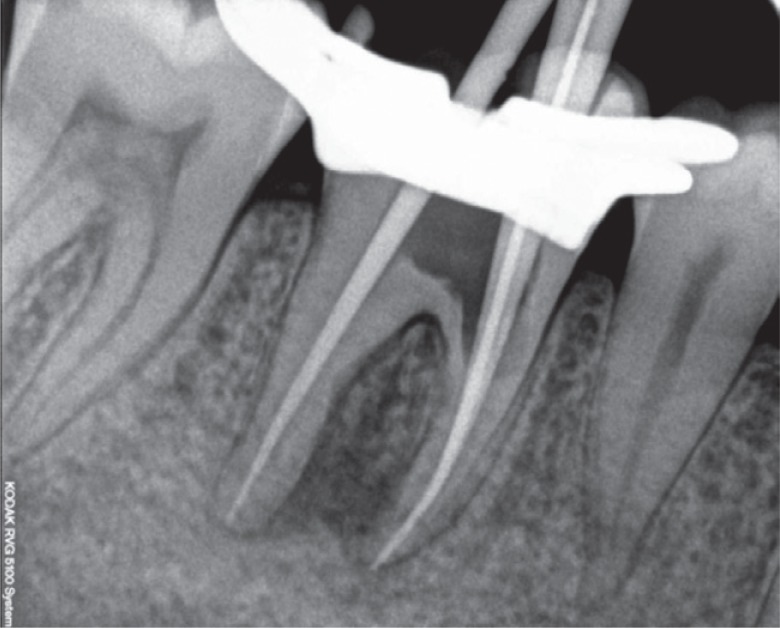

Figure 3). Following the cleaning and shaping of the canals, calcium hydroxide (Avue Cal, Dental Avenue, Param Enterprises, Pune, India) was placed as an intracanal medicament for one and half months. The dressing was changed every two weeks. Once the tooth demonstrated signs of radiographic healing of the periapical lesion and the absence of symptoms, the obturation was completed with cold lateral condensation and resin-based sealer (AH Plus, Dentsply DeTrey, Konstanz, Germany,

Figures 4 and

5) and the tooth was temporised. Since the remaining amount of dentin around the mesial orifice and on the floor of the chamber was compromised and nearly approached the furcation, we decided to place Biodentine (Septodont, Saint-Maur-des-Fossés, France) as a dentin substitute base. The following day, a 2 mm thick layer of Biodentine was placed on the floor and around the mesial orifice (

Figure 5Post-obturation radiograph.